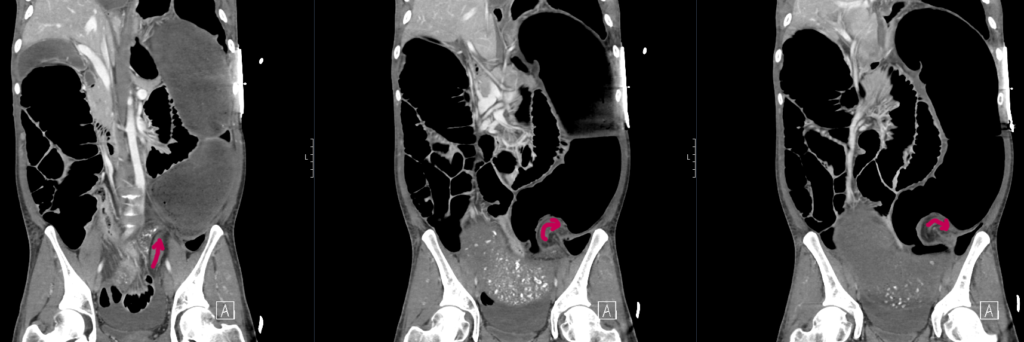

A CT mesenteric angiogram is urgently arranged.

CT mesenteric angiogram

There is evidence of a sigmoid volvulus.

The proximal large bowel as well as small bowel loops are dilated suggestive of an incompetent ileocaecal valve.

The abdominal aorta as well as the origins of the common iliac arteries and external iliac arteries are compressed by dilated bowel loops however remain patent and there is satisfactory flow distally to the common femoral and superficial femoral arteries.

There is narrowing of the proximal coeliac trunk likely due to compression by the median arcuate ligament. The coeliac trunk and its major branches are otherwise patent. The SMA and IMA are patent.

Comment: Acute sigmoid volvulus with severe bowel obstruction. The dilated bowel loops are significantly compressing the abdominal aorta and pelvic arteries as above. Urgent surgical review recommended.